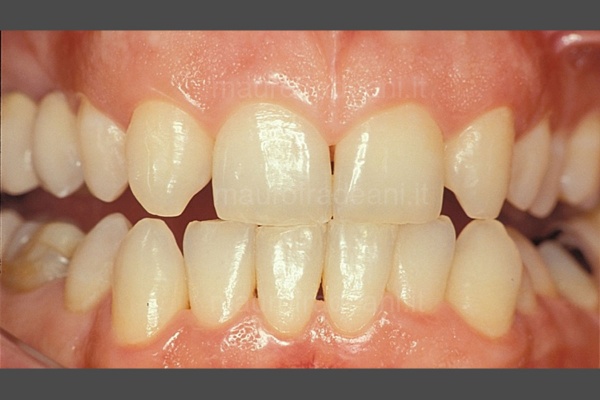

3/4: Intraoral view of the cemented all-ceramic restorations. Thanks to the esthetic-functional rehabilitation, the correct occlusion was restored by re-establishing suitable lengths and appropriate dental morphologies, as well as a much more pleasant color.

4/4: At the end of the treatment, the restored smile fully meets the patient’s esthetic expectations.